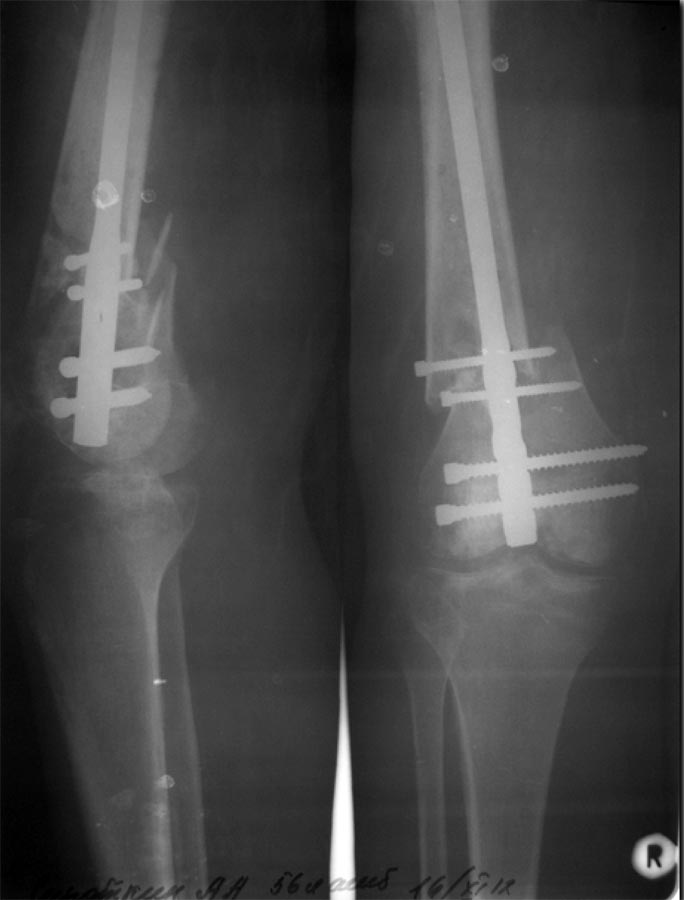

Разрешите представить Вам следующий случай.Пациент С., 55 л, получил открытый сегментарный перелом бедренной кости 24.07.12 в результате столкновения скутера с автомобилем (упал со скутера). Доставлен в наше отделение. В экстренном порядке- наложение стержневого АВФ, ПХО раны. После ее заживления,17.08.12- ретроградный БИОС универсальным бедренным штифтом ChM. Блокирующие винты перепроведены 05.09.12 (у оператора не хватило опыта-не попал в отверстия). Выписан 28.09.12. В настоящий момент беспокоят боли в коленном суставе, отек всей конечности, отсутствие полного объема движений в суставе, субфебрилитет. Ходит на костылях с нагрузкой примерно 15 % массы тела, увеличить нагрузку мешает боль. Местная температура не повышена, в полости сустава жидкости нет.Результаты анализов-СОЭ, СРБ пока неизвестны. Что делать?

На мой взгляд, боли в суставе возможны по двум причинам: ось бедра не востановлена, имеется вальгусная отклонение голени, из-за чего неравномерное распределение нагрузки на уже артрозный сустав! Или же изначальное повреждение внутренних структур сустава. Но складывается еше ощущение, что гвоздь не добит сантиметров на 1,5. На мой взгляд, целесообразно произвести диагностическую артроскопию. Исправлять ось, реостеосинтез!

Существуют этапные снимки, по которым можно оценить ось бедра во фронтальной плоскости- она правильная, нарушена ось промежуточного фрагмента. Насчет выстояния конца гвоздя- сам об этом думаю, но опасаюсь, что при переблокировании развалится дистальный отломок (он уже и так как дуршлаг). Хотелось бы услышать мнение уважаемого Александра Николаевича Челнокова.

Насчет оси - гвоздь в дистальном отломке идет несоосно ему, на уровне перелома гвоздь ближе к латеральной стенке, то есть эпиметафиз смещен медиально. По профилю - и кзади. Похоже, и укорочение есть.